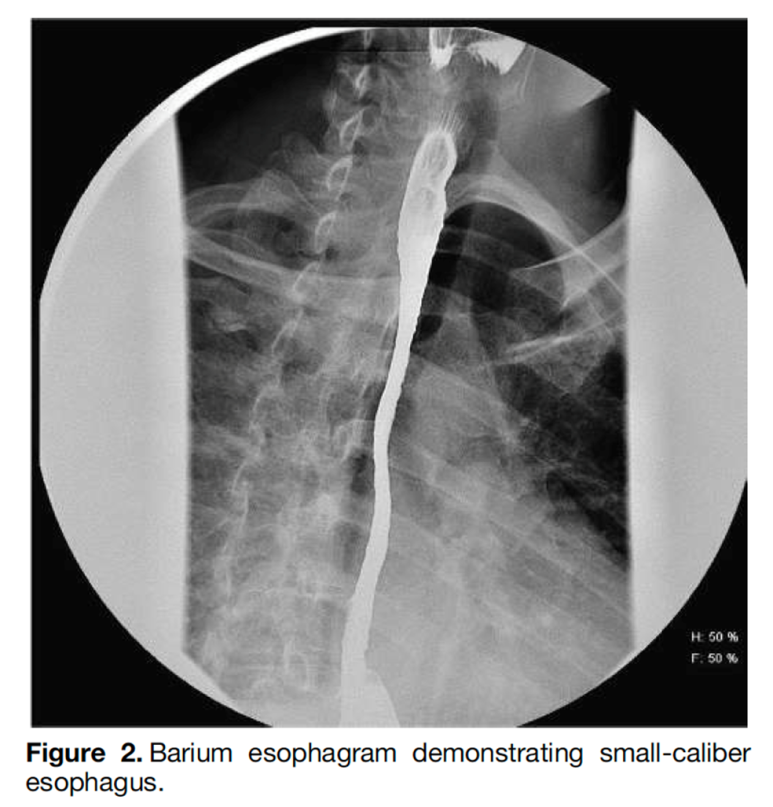

한편, 유럽에서는 10만명 당 13-49명 발생한다고 보고하고 있으며, 주로 30-50세 사이의 성인 남성에게 자주 발생한다고 보고하고 있습니다.진단방법으로는 바륨스터디를 시행하는데, 비특이적이며 내시경 소견이 중요합니다.

이 염증반응에 의해 혈관의 신생합성이 증가하여 근육층이 두꺼워지고 섬유화가 진행되어 식도의 운동성을 저하시키고 내강이 좁아지는 담보이기 때문에 음식통과를 위한 경로가 적어집니다.

경과기 전에 말씀드렸다시피 먼저 호산구 식도염의 초기 증상은 염증 반응입니다. 이 염증 반응은 치료하지 않을 경우 esophageal remodling을 통해 내강이 좁아지고 기능 저하가 발생합니다. 하지만 항염증 요법을 시행할 경우, 호산구 식도염 질병의 진행 결과를 제한할 수 있다는 일부 보고가 발표되었습니다.이를 바탕으로 질병 발생 초기 또는 소아 청소년에서 발생한 호산구 식도염의 경우 약물치료 또는 식사치료를 할 수 있으나 이미 병변이 진행 중이고 섬유화가 진행된 경우 식도확장시술 외에는 다른 약물, 식생활료요법이 효과적이지 않습니다.